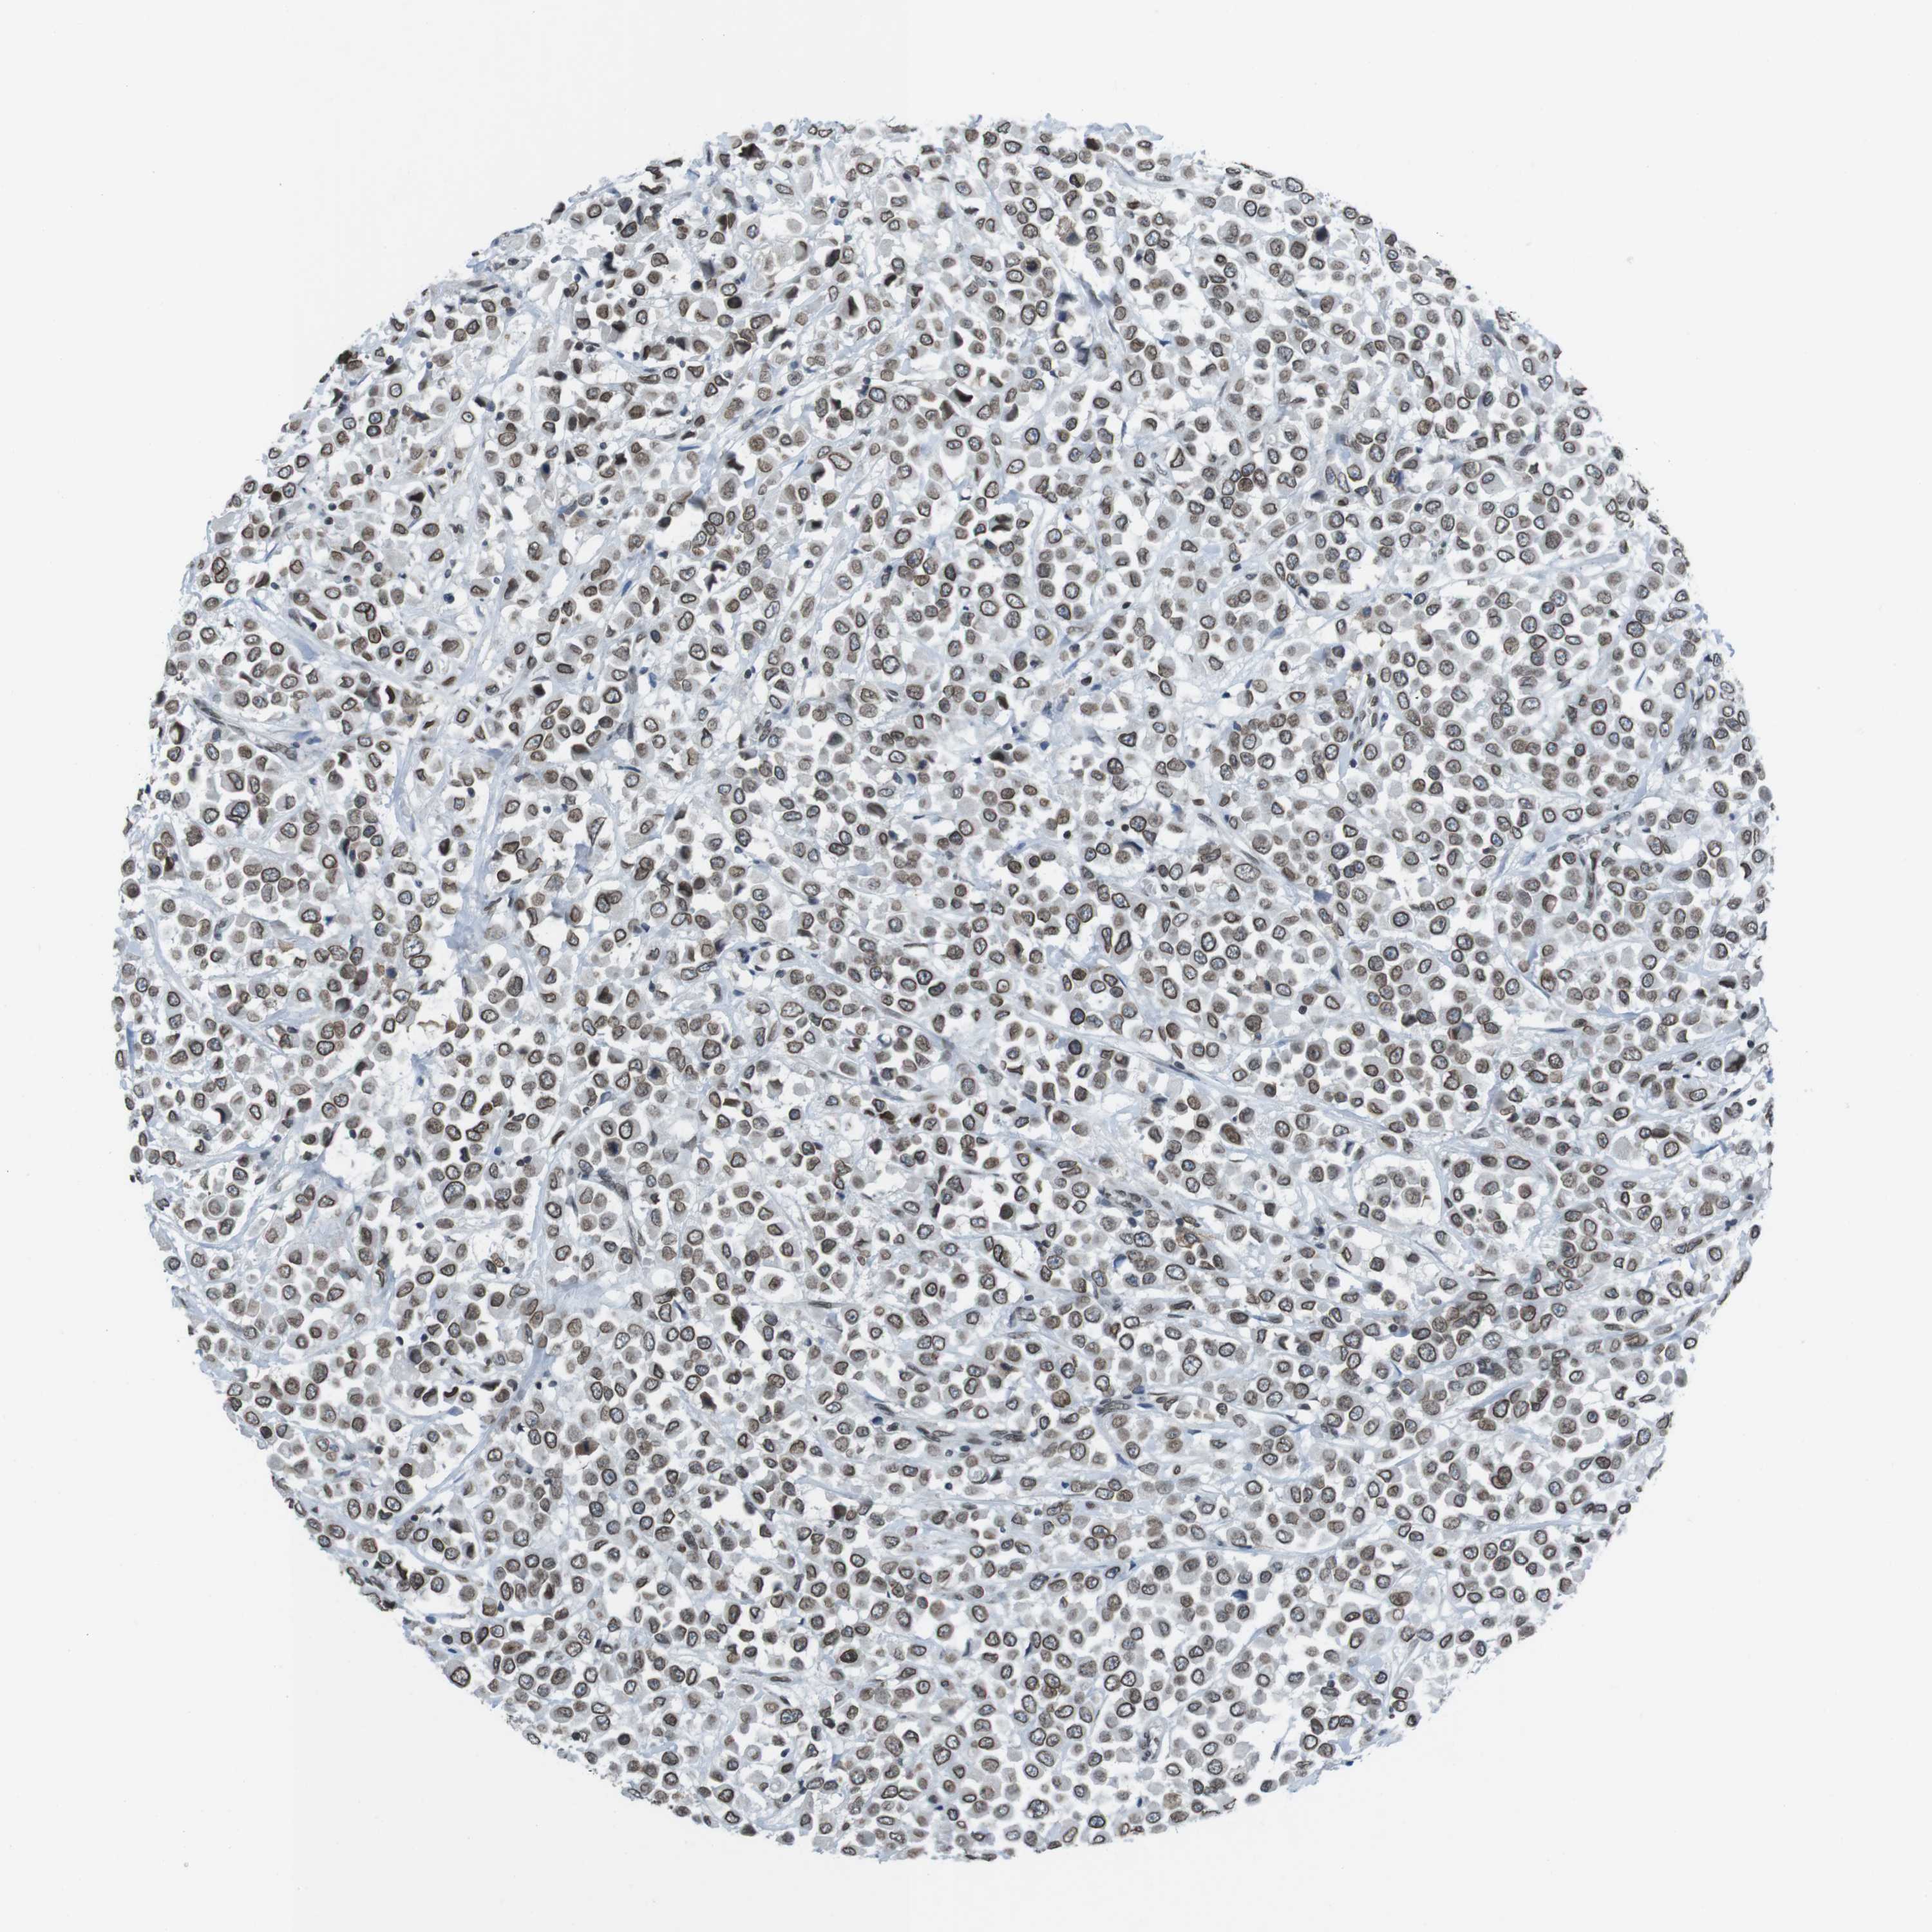

BRCA TCGA BRCA VALIDATION PROTEIN EXPRESSION